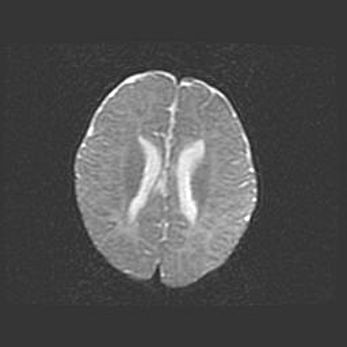

Церебральная ишемия II.

Возраст: 5 дней

Вес: 3400 г

Пол: женский

Окружность головы: 35 см

Срок гестации: 39 недель

Церебральная ишемия – это заболевание, характеризующееся недостаточностью (гипоксией) либо полным прекращением (аноксией) снабжения мозга кислородом по причине закупорки одного или нескольких сосудов. Это приводит к  что метаболическим расстройствам различной степени тяжести в тканях головного мозга, развитию коагуляционных некрозов и гибели нейронов.